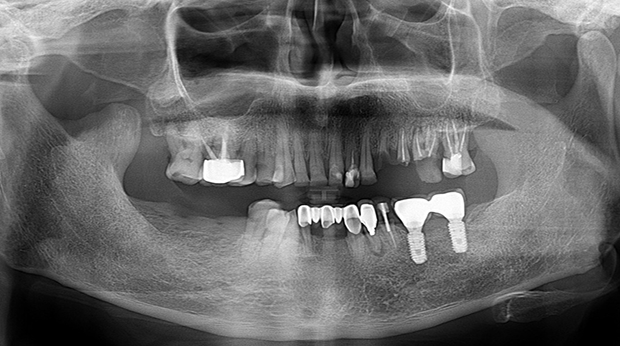

의식하진정법(수면마취)/임플란트

수술 담당 구강악안면외과 전문의

고난도 수술 진료

임플란트와 사랑니 발치는 외과적 시술로 잇몸을 절개하는 외과적 시술은

짧으면 짧을 수록 시술 후 붓기와 통증이 최소화됩니다.

치과의사 경력 14년차 구강외과 전문의가 빠르고 안전하게, 아프지 않게 수술해 드립니다.